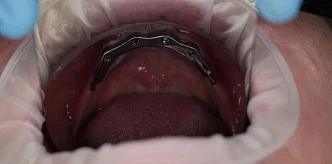

Установили 4 импланта сверху и 4 импланта снизу

- Имплантация, установка временного протеза

- Проверка стабильности установки имплантов

- Снятие слепков

- Установка постоянного протеза